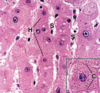

Liver

Mitochondria in Liver

Liver Hepatocytes